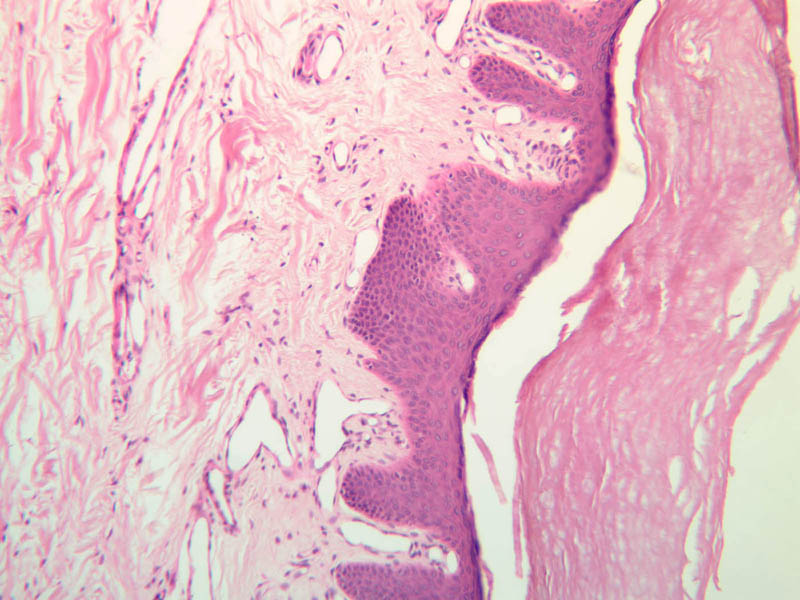

For general orientation, note that skin has two components, epidermis (a stratified squamous epithelium) and dermis (a connective tissue layer beneath the epidermis). Epidermal ridges project into the dermis, enclosing between them the highly vascular dermal papillae. Beneath the dermis lies the subcutaneous tissue, a loose layer of connective tissue, fat, blood vessels, and nerves. The skin appendages are situated partially in the dermis and partially in the subcutaneous layer. The skin consists primarily of two cell types; a keratin-producing epithelial cell (keratinocytes) and a pigment cell of neural crest origin (melanocyte). Langerhans cells are also present. These are believed to be antigen presenting cells of the epidermis. The keratinocytes exhibit morphological and functional stratification from base to surface of the epithelium and thus provide a basis for distinguishing several layers of the epidermis.

Examine slide A-50 (fingertip, H&E [2.5x, 10x-labeled, 20x, 40x-labeled] [20x, 40x] [10x, 20x, 40x] [20x, 20x, 40x]), and study the morphology of five layers of thick skin. The deepest part of the epidermis comprises the stratum basale which provides the cells required for continual renewal of the epidermis. This stratum is composed of a single layer of columnar or cuboidal epithelial cells attached to the basement membrane.

Superficial to the stratum basale is a multi-cellular layer known as the stratum spinosum, consisting of polyhedral cells that have a "prickly" or spiny appearance (A-50, langerhans cells [10x, 20x-labeled, 40x-labeled] [40x, 40x-labeled, 40x, 40x-labeled]; A- 48, abdominal skin, H&E [10x, 20x, 40x] [40x, 40x, 40x, 40x]). The spiny cells are separated by intercellular spaces that are bridged at numerous points by cytoplasmic processes, which in turn are bound together by desmosomes. The cytoplasmic processes projecting on all sides from the cells give them the spiny appearance to which the name refers. These are best seen under high power. Langerhans cells can also be found in this layer.

Superficial to the stratum spinosum is a layer of flattened cells with coarse, deeply-stained cytoplasmic granules, the stratum granulosum (slide A-50 [40x] [40x, 40x] [40x-labeled, 40x, 40x]). These are keratohyalin granules and evidently represent a stage in the keratinization of the epidermal cells. Note that the nuclei of the more superficial granular cells appear dense and pyknotic, foreshadowing their disintegration and the resultant death of the cells.

The stratum lucidum is often considered to be a subdivision of the stratum corneum. This layer is evident only in thick (glaborous) skin. It appears as a clear band beneath the stratum corneum. Cells of the stratum lucidum are well advanced in the process of keratinization. Consequently, the nucleus and many of the cytoplasmic organelles become disrupted and disappear as the cells become filled with the intracellular protein keratin. In many specimens, there is a separation artifact at this point. The outermost layer of the epidermis is called the stratum corneum and is composed of fully cornified (keratinized) remnants of epithelial cells ([40x]). It has a basketweave appearance. The close union of the resulting scales with each other, and their content of insoluble protein and extracellular lipids, provides a barrier to diffusion between the body and its external environment.